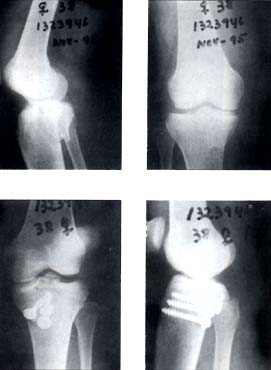

En 14 casos (88%) el tratamiento fue quirúrgico, el abordaje fue posterior entre las dos cabezas del gastrocnemio y en dos pacientes (12%) se realizó un doble abordaje anterior y posterior. La osteosíntesis se realizó con tornillos de esponjosa en cuatro pacientes (25%) como se ilustra en la figura 2 y con placa en T en 10 pacientes (62%) como se ilustra en la figura 3.

Fig 2. Paciente de sexo femenino de 38 años de edad con fractura del platillo tibial posteromedial y fijación con tres tornillos de esponjosa.